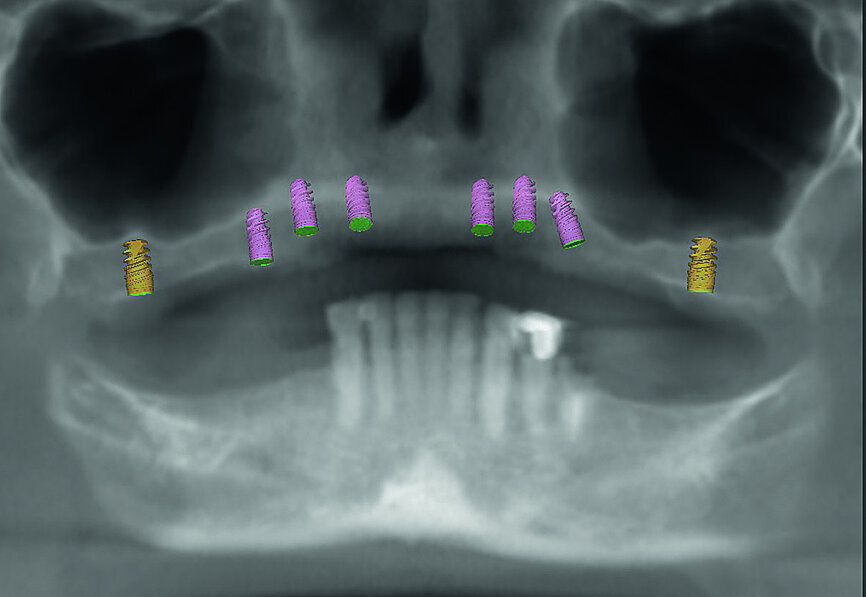

Fig. 3: Proposed treatment of maxillary arch.

Fig. 4: Proposed treatment of mandibular arch.

Fig. 5: Dentofacial analysis of proposed implants in maxillary arch.

Fig. 6: Dentofacial analysis of proposed implants in mandibular arch.

The patient returned for the records appointment, where maxillary and mandibular impressions were taken so that immediate temporary dentures could be fabricated for delivery at the surgical appointment. CBCT scanning was performed using a CS 8100 3D scanner (Carestream Dental) to provide the information needed for virtual treatment planning. The 3-D data obtained from the CBCT scans was used to determine the ideal length, width and placement of the implants in the key positions of the patient’s edentulous arches, including the first molar, first premolar, canine and central incisor regions (Figs. 3–6). From the digital treatment plan created by 3D Diagnostix, bone-level surgical guides were produced for the maxilla and mandible (Figs. 7 & 8).